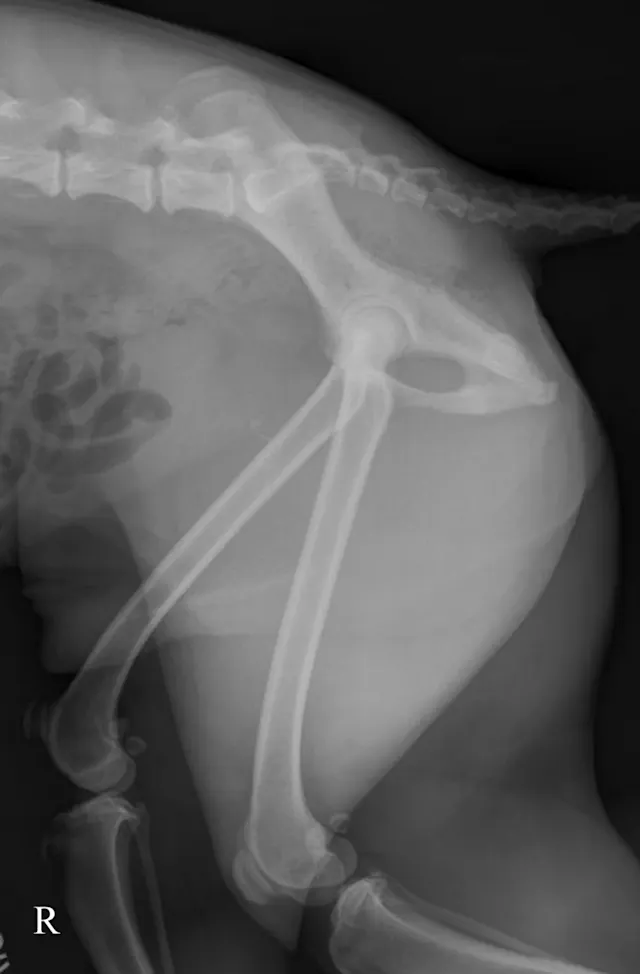

The lateral radiograph is obtained with the patient in lateral recumbency and the hindlimbs separated (Figure 3A). A foam positioning device is placed between the limbs or under the "up" leg to keep the femur parallel to the table. The forward limb (typically the limb closest to the imaging plate) is labeled. The corresponding normal lateral radiograph is shown in Figure 3B. In Figure 3C, the femoral head (arrow) of the cranially positioned right limb is luxated craniodorsally.